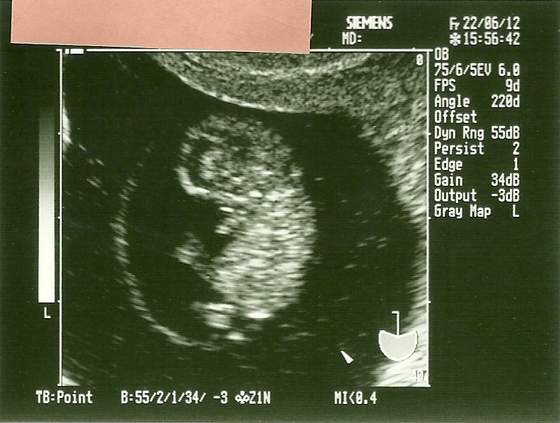

skanowanie0001.jpgskanowanie0003.jpg

Nooo to mój maluch :) 9 tydzień z haczkiem. Teraz wizyta 10 go i będzie równiśki 12 tydzień i genetyczne badanko :)